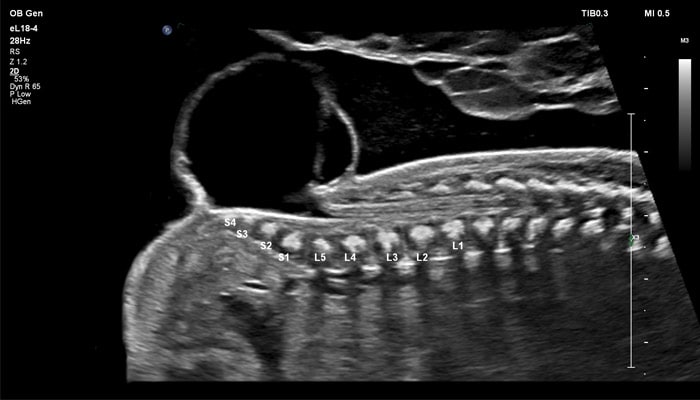

В случае аномалий позвоночника, оценка ануса важна, чтобы исключить аноректальные пороки развития, которые могут быть частью более широкой группы аномалий, известных как VACTERL (аномалии позвоночника, атрезия ануса, пороки сердца, трахеопищеводный свищ, аномалии почек, дефекты лучевой кости). Исследования в США показали, что очень высокое качество изображений еL18-4 повышают уверенность клиницистов в исключении аноректальной аномалии плода.

Во II триместре беременности высокая разрешающая способность eL18-4 позволяет детально изучить структуру органов и тканей и увидеть многие нюансы, которые при работе другими датчиками не обнаруживались или становились очевидны в более поздние сроки. Например, у 19-недельного плода визуализируется перегородка носа, мышцы языка, диафрагма между грудной и брюшной полостью, на 20-й неделе чётко определяются оболочки спинного мозга и уретра, а на 24-й – хорошо дифференцируются корень лёгкого, борозды и извилины мозжечка и многие другие структуры.